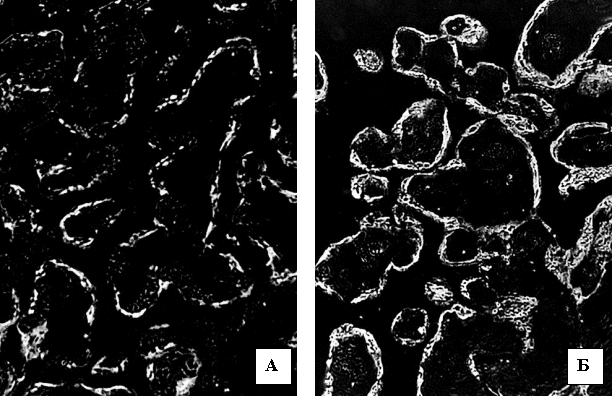

У проміжок вагітності 13-20 тижнів

таке світіння в контрольній групі очевидно посилювалося (у середньому –

84,4±2,04), а при ЗДАВ воно ставало ще більш інтенсивним (127±2,93). Розбіжність

між групами дослідження за критерієм Mann-Whitney була

вірогідною (p<0,001). Описані зміни

проілюстровані рисунком 1.

Рис. 1. Світіння цитоплазми трофобласта хоріальних ворсинок після

обробки люмінолом при довжині хвилі 425 нм. А) контрольна група. 18 тижнів

вагітності. Б) залізодефіцитна анемія. 18 тижнів вагітності. Мікроскоп ЛЮМАМ-8.

Об.20х. Ок.10х.